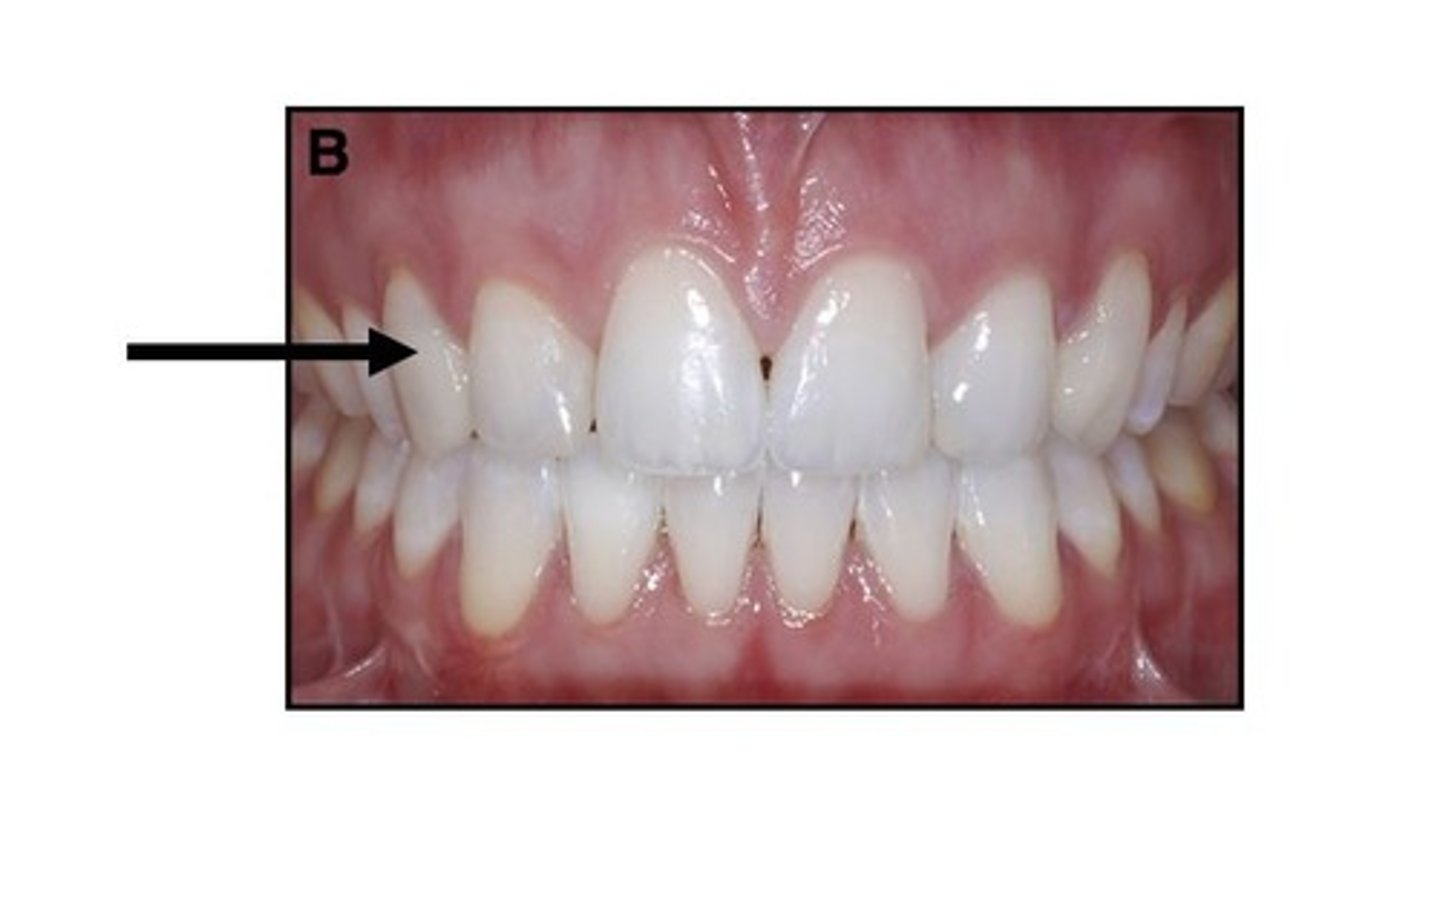

Supernumerary tooth

What dental anomaly is this (extra tooth in maxillary anterior region)?

<p>What dental anomaly is this (extra tooth in maxillary anterior region)?</p>